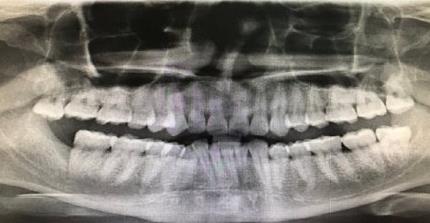

上頜智齒,下頜沒有